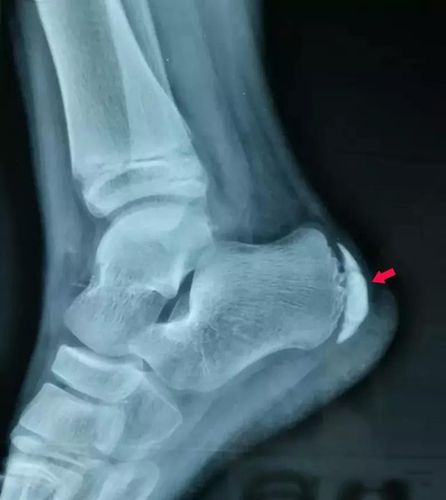

跟骨骨骺炎x线影像图

跟骨骨骺炎x线影像图,正常儿童跟骨骨骺图片

支持大家的意见:跟骨骨骺炎. 表现: 跟骨骨骺密度不均匀增高

跟骨骨骺图片

跟骨骨骺炎

儿童跟骨骨骺炎x线

儿童跟骨骨骺炎图片

跟骨骨骺炎位置图

跟骨骨骺